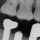

Dental implants have revolutionized restorative dentistry, giving patients reliable, long-lasting solutions for missing teeth. But sometimes, even the most well-placed implants encounter challenges—especially when components like screws or abutments break inside the implant. That’s where Implant Mechanical Rescue (IMR) comes in.

Implant Mechanical Rescue is a highly specialized service focused on retrieving broken or damaged components from inside a dental implant. This includes:

- Broken screws or abutment fragments retained inside the implant

- “Stripped screws”, where the drive geometry of the screw head is lost and the screw cannot be removed with conventional tools

IMR is a precision procedure. It requires careful planning and technique to remove the damaged piece without harming the implant or surrounding bone. The goal is to preserve the integrity of the existing implant so it can be restored afterward.